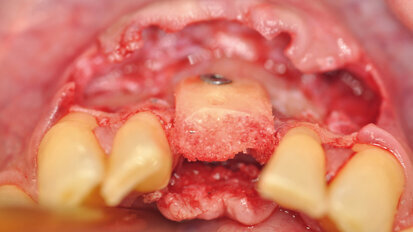

Management kosti a měkkých tkání při komplexní rekonstrukci jednoho zubu implantátem

Rekonstrukce jednoho frontálního zubu implantátem bývá pravděpodobně největší estetickou výzvou pro praktického zubního lékaře. Správné ...